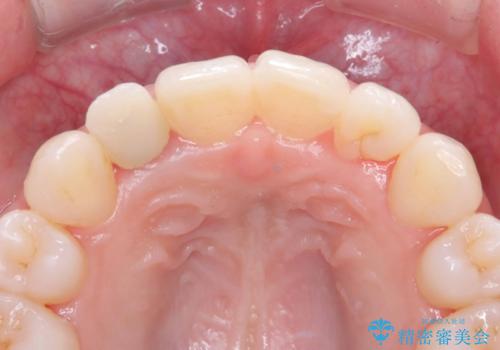

歯と被せ物の境を歯肉縁下0.5㎜に設定して形成を行いオールセラミッククラウン(スペシャル)で治療を行いました。

- 税込165,000円(オールセラミッククラウン.スペシャル154,000円+仮歯11,000円)費用は治療当時の料金となります